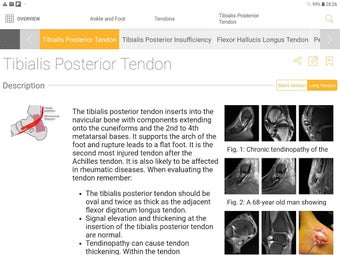

Die Basisversion liefert die wesentlichen Fakten, die immer noch kurz und prägnant sind. Die Fakten konzentrieren sich auf die klinisch relevanten Aspekte des Zustands des Patienten.

Die Pro-Version enthält mehr als 4.000 hochwertige Bilder von herausragender Bildqualität, die den Text veranschaulichen. Sie sind so konzipiert, dass sie dem Leser einen schnellen Überblick über die wichtigsten Informationen zum Zustand geben.